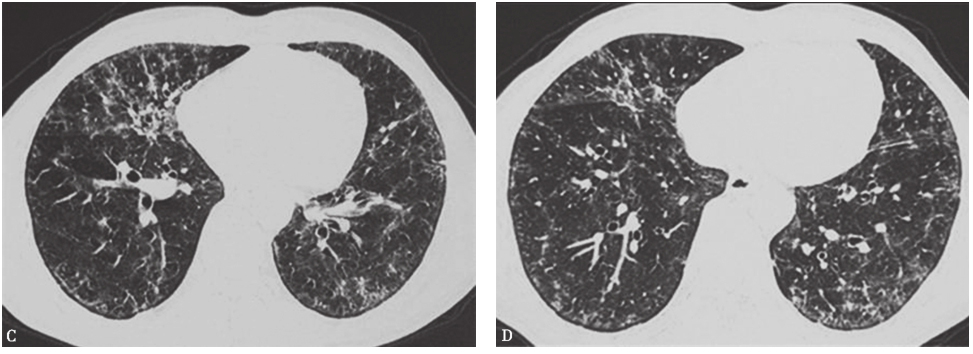

肺部感染性疾病指包括终末气道、肺泡腔及肺间质等在内的肺实质炎症。按病因可分为细菌性肺炎、病毒性肺炎、非典型病原体肺炎(军团菌、肺炎支原体、衣原体感染)、真菌性肺炎、肺结核、其他病原体(立克次体、弓形虫、肺孢子菌、寄生虫等)所致肺炎。临床表现为发热、咳嗽、咳痰,部分可有气促、胸痛、咯血等,体征可有湿啰音,影像学有肺浸润改变。病情严重者有气体交换障碍。肺部感染性疾病可根据症状、体征、影像学表现等做出临床诊断,确诊需依据病原学检查结果。本例患者为中年男性,慢性病程,病程中无发热,主要临床表现为咳嗽、气喘,抗感染治疗效果不佳,结合胸部影像学表现,与普通感染表现不符合。患者平时身体健康,无结构性肺病等慢性病病史,特殊病原体感染可能性亦不大。患者CT特点为两肺磨玻璃影、弥漫性小结节影,须注意与肺结核尤其是血行播散型肺结核鉴别。后者影像学表现为肺野内多发均匀分布的小颗粒状阴影,病变亦可相互融合,呈小斑片状阴影,部分边缘模糊,有的病变呈增殖硬结,部分亦可见纤维化索条状阴影(图2)。本例患者无结核相关发热、消耗等表现,故患肺结核可能性亦不大。

图2血行播散型肺结核胸部CT表现

胸部CT可见两肺弥漫小结节影,大小、分布、密度较均一